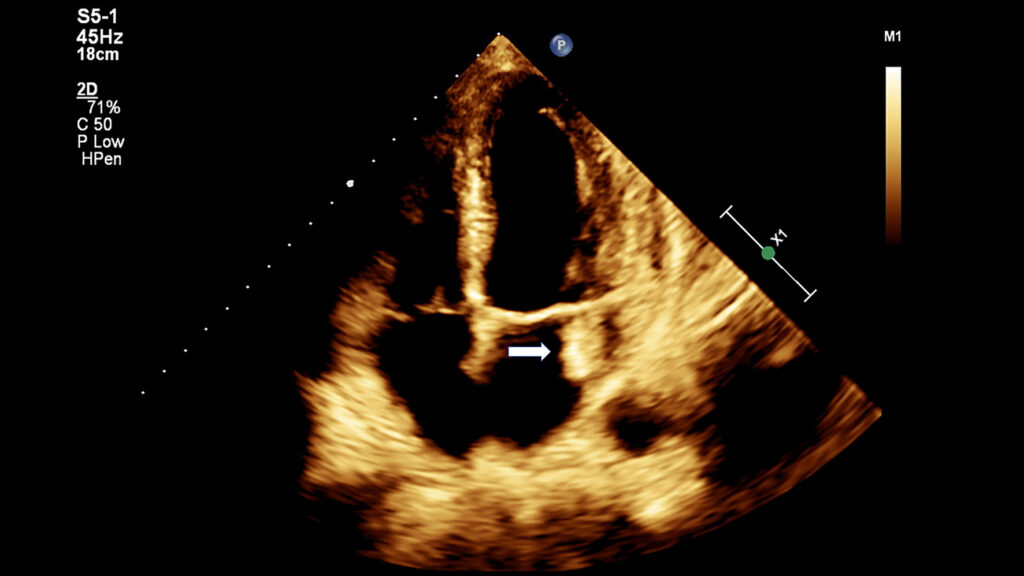

A endocardite infecciosa (EI) sempre impôs desafios ao universo médico, os quais foram respondidos pelas mais recentes inovações e esforços persistentes. Segundo Habib et al., “A endocardite infecciosa ainda é uma doença que envolve riscos à vida, com frequentes desfechos letais, apesar das profundas mudanças em seus perfis clínicos, microbiológicos, de imagem e terapêuticos”.

Diversos fatores influenciam as peculiaridades da doença. A Índia é um país em desenvolvimento, cujo sistema de saúde é de natureza muito polarizada. Nas aldeias, há centros rurais de Atenção Primária com instalações básicas, que prestam cuidados de saúde de nível muito primários, estendendo-se ao centro de excelência hospitalar com os últimos avanços da área médica. O ponto crucial é o tempo que leva para um paciente chegar ao centro adequado para as intervenções corretas e, ainda mais importante, o diagnóstico de EI deve ser estabelecido pelos médicos da Atenção Primária o quanto antes. O fator socioeconômico desempenha um papel fundamental no desfecho. Todas as três questões representam um desafio ainda maior, principalmente em um país tão grande quanto a Índia. Sengupta et al. concluíram que fatores socioeconômicos influenciam o perfil clínico de pacientes com EI em todo o mundo, levando a atrasos no diagnóstico e a menos casos de cirurgia. Já Gupta et al. mostram observações sobre EI, como aumento da idade e proporção de pacientes sem histórico de doenças cardíacas, melhores taxas de positividade em exames sanguíneos e aumento de infecções estafilocócicas, além do aumento do uso de ecocardiograma transesofágico (ETE) e das altas taxas de cirurgias eletivas.